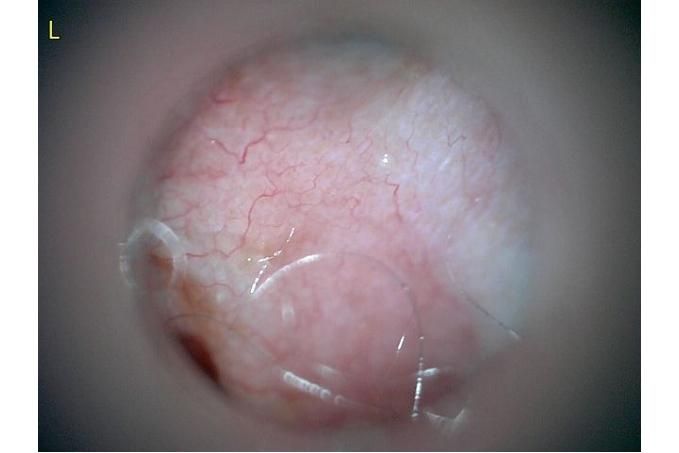

사진만 보고 확진할 수는 없지만 지금 올려주신 귀는 적어도 오른쪽은 정상으로 보이기 어렵습니다 왼쪽은 비교적 연분홍에 가까워 보이지만 오른쪽은 털과 분비물이 많이 차 있고 피부가 자극받은 듯한 모습이라 외이염 가능성을 먼저 생각하게 됩니다 그리고 질문자님이 적어주신 머리 털기 하루 여러 번 귀 만질 때 통증 솜만 닿아도 예민함 귀 긁기 같은 증상은 외이염에서 흔한 신호입니다